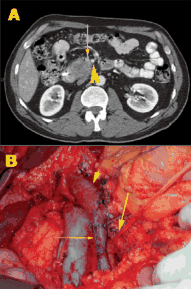

Patient with pancreatic adenocarcinoma before (A) and during (B) surgery.